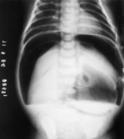

对早产儿(已开始喂养)的大便作隐血筛查或还原物检查可帮助早期诊断坏死性小肠结肠炎。早期X线检查无特异性,仅显示肠梗阻,但是重复X线检查,位置固定的扩张肠段提示坏死性小肠结肠炎的存在,坏死性小肠结肠炎的X线诊断为肠壁积气和门静脉积气,气腹提示肠穿孔,需要急诊外科手术治疗。